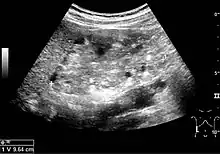

Angiomyolipoma seen as a hyperechoic mass in the upper pole of an adult kidney on renal ultrasonography.